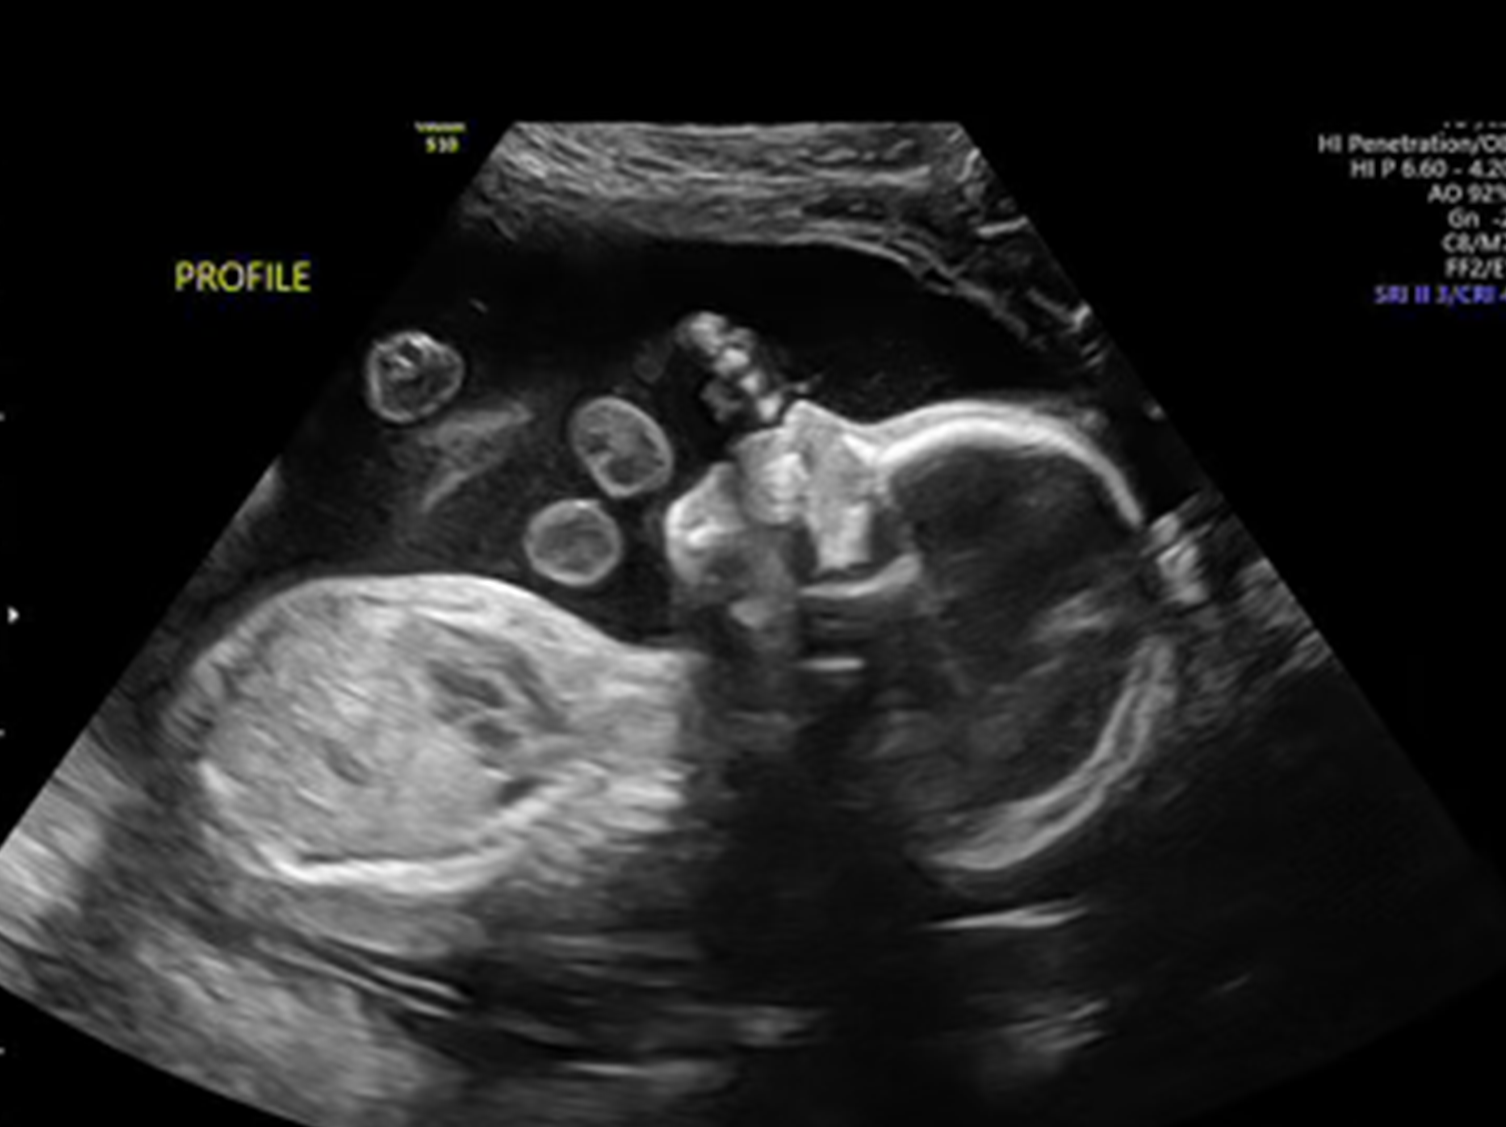

Our 3D and 4D ultrasounds provide a unique opportunity to see your baby in incredible detail. 3D ultrasounds offer clear, three-dimensional images, while 4D ultrasounds add the dimension of time, capturing your baby's movements in real-time. This advanced imaging allows you to see everything from your baby’s tiny features to their playful kicks and stretches.